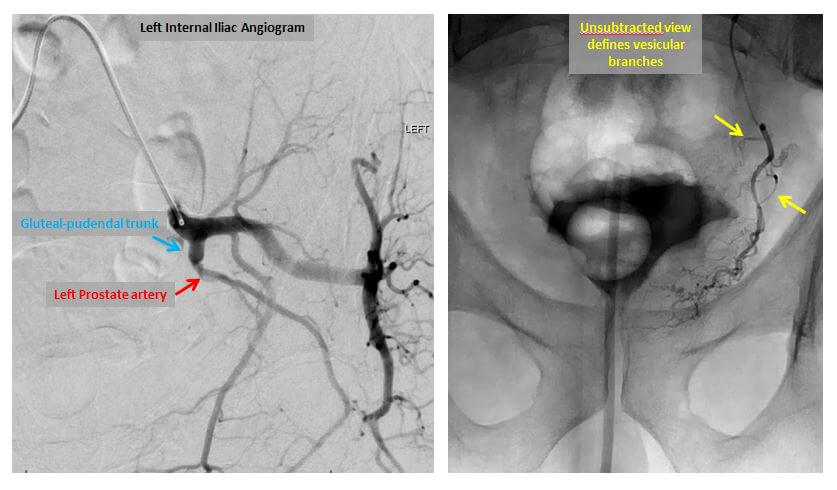

Left internal iliac (left image) and prostatic artery angiograms (right image).

Once the prostatic arteries have been identified, the catheter is repositioned under X-ray guidance and moved into the left prostatic artery. X-ray dye is again injected in order to confirm the position of the catheter. Once this is done, small particles or microspheres are injected into the catheter in order to stop the flow of blood within the left prostatic artery. Once it is injected, the microspheres induce inflammation, slow blood flow, and create clot formation within the artery. When blood flow has stopped within the left prostatic artery, the catheter is repositioned into the right prostatic artery and the procedure is repeated. In our experience, most patients can be embolized with a single catheter entering the arterial system on the right side; a second catheter placed into the left common femoral artery is necessary only in the most difficult cases. Once the embolization is complete, the catheter is removed and a seal is placed into the right common femoral artery to insure that there will be no bleeding from the site. The length of the procedure is variable and highly dependent upon the complexity of the arterial anatomy.